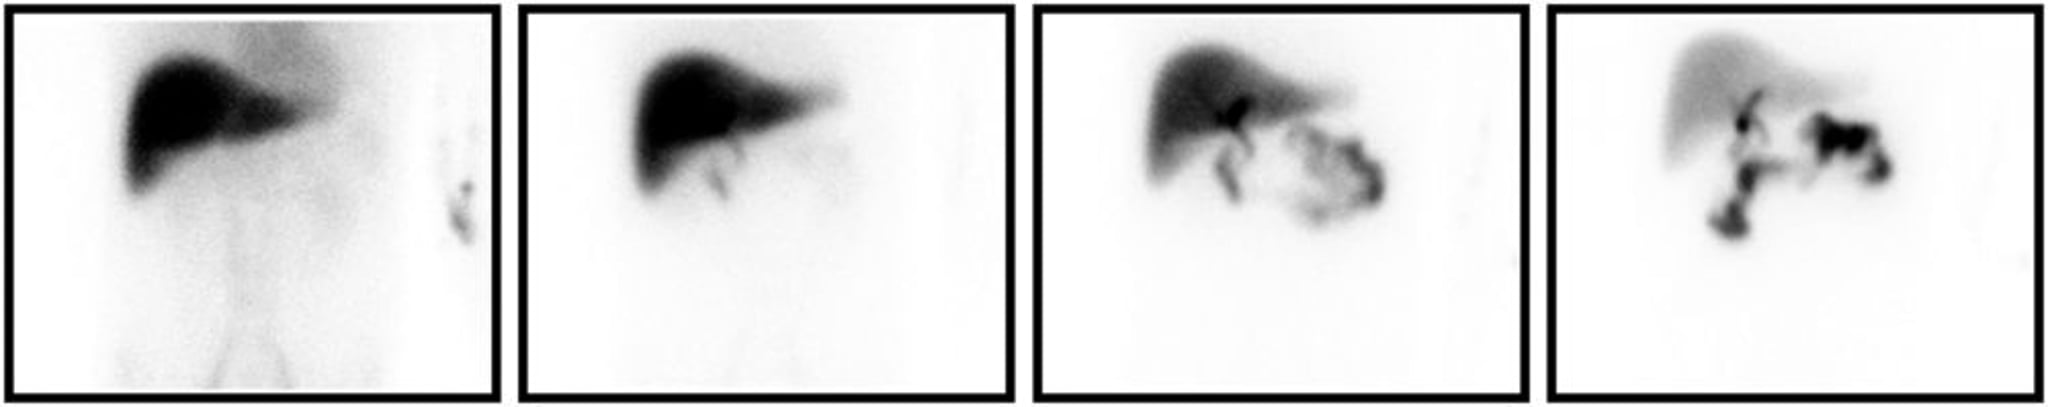

Varredura HIDA

Varredura HIDA consistente com colecistite. As imagens mostradas da esquerda para a direita são tiradas em 5, 15, 30 e 60 minutos após a injeção do radiomarcador. Mesmo em momentos mais tarde, não há preenchimento da vesícula biliar.